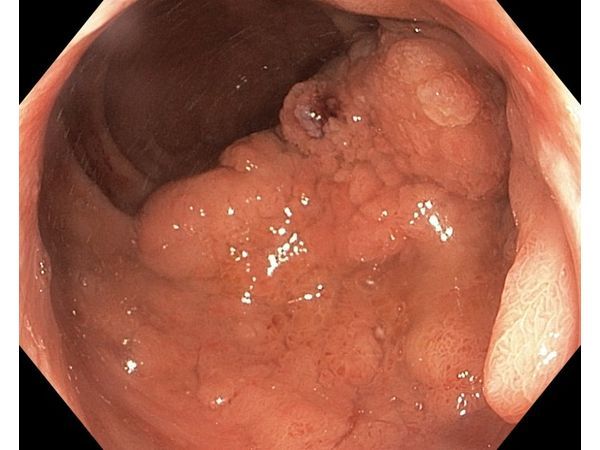

Пациенту сделали повторную колоноскопию, но уже на оборудовании экспертного класса. Оно снимает видео в высоком разрешении (HD) и позволяет улучшить изображение с помощью современных методик: двойного фокуса и режима узкого спектра.

По результатам этого обследования выявили плоскую поверхностную опухоль гранулярного (узловатого) типа (LST-G-NM). Образование длиной 70 мм начиналось в анальном канале и доходило до ампулы прямой кишки. Оно поразило меньше 50 % окружности органа.

Хотя предыдущая биопсия не обнаружила признаки малигнизации (озлокачествления), по данным нового, более качественного визуального обследования возникло подозрение, что опухоль стала злокачественной, но без убедительных признаков инвазивного роста — на первый взгляд образование не прорастало в окружающие ткани.